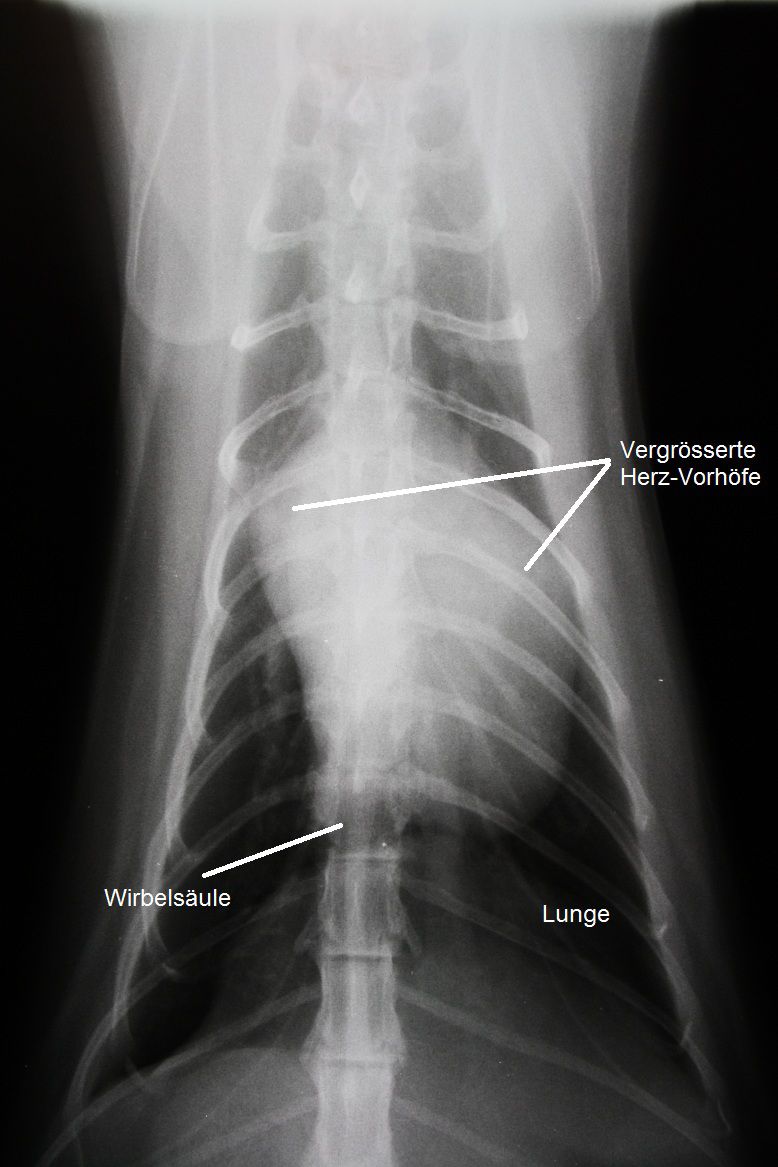

Schon in der Nacht wurden Röntgenbilder des Brustkorbes angefertigt, welche ein vergrössertes Herz mit übermässig grossen Vorhöfen zeigt.

Die Röntgenbilder weisen auf eine Herzerkrankung hin, welche zum Verschluss der Körperschlagader geführt haben könnte. Das Herz wird mittels Ultraschall genauer untersucht, und es zeigt sich, dass die Muskulatur der Herzkammern sehr stark verdickt und die Vorhöfe stark erweitert sind. Eine Diagnose einer Hypertrophen Kardiomyopathie (HCM) wird gestellt.